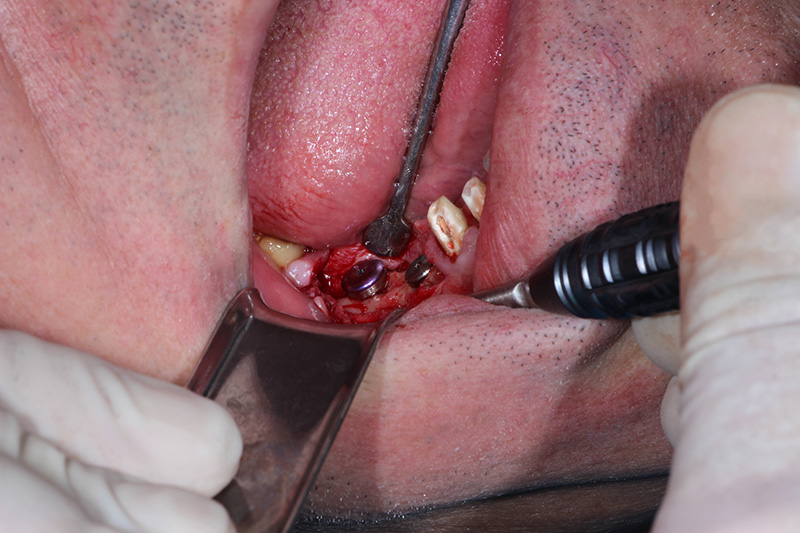

26-ого октября в учебном центре Стом-Лайн был проведен мастер-класс на тему «Закрытый и открытый синус-лифтинг при имплантации, с использованием имплантатов Thommen Medical». Мастер-класс провел главный врач-стоматолог клиники «Нюанс» в Москве Мхитар Казарян.

Мастер-класс начался с представления швейцарских имплантатов Thommen Medical, официальным предтсвителем которых является клиника Стом-Лайн. Далее были проведены обсуждения предстоящей операции и исследования компьютерной томографии, после чего участники смогли присутствовать на операции или следить за ней из учебного центра.

Во время операции доктор Казарян представил на практике особенности и преимущества имплантатов Thommen Medical.